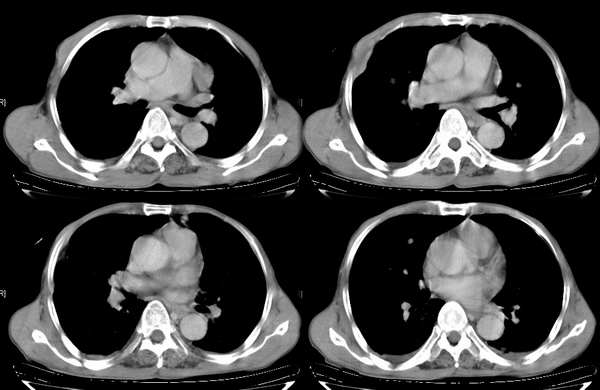

男,74岁,甲状腺肿30余年。现右颈部出现新肿块,疼痛,感乏力。

右颈部巨大软组织肿块影,范围较广,上至下颌角,下至颈静脉切迹。其最大层面位于右侧甲状腺区。肿块密度不均,其中有坏死液化区和班片状钙影,增强扫描见肿块实质区有强化。邻近结构挤压移位,部分结构侵蚀破坏,右侧多个颈深淋巴结肿大。两肺弥漫分布小结节影,以胸膜下为主,其大小不等,边缘光整。右侧胸壁亦见软组织结节影,纵隔多个淋巴结肿大及两侧锁骨上淋巴结肿大。

意见:右侧甲状腺癌并两肺、胸壁、纵隔淋巴结、颈深淋巴结、锁骨上淋巴结等广泛转移。